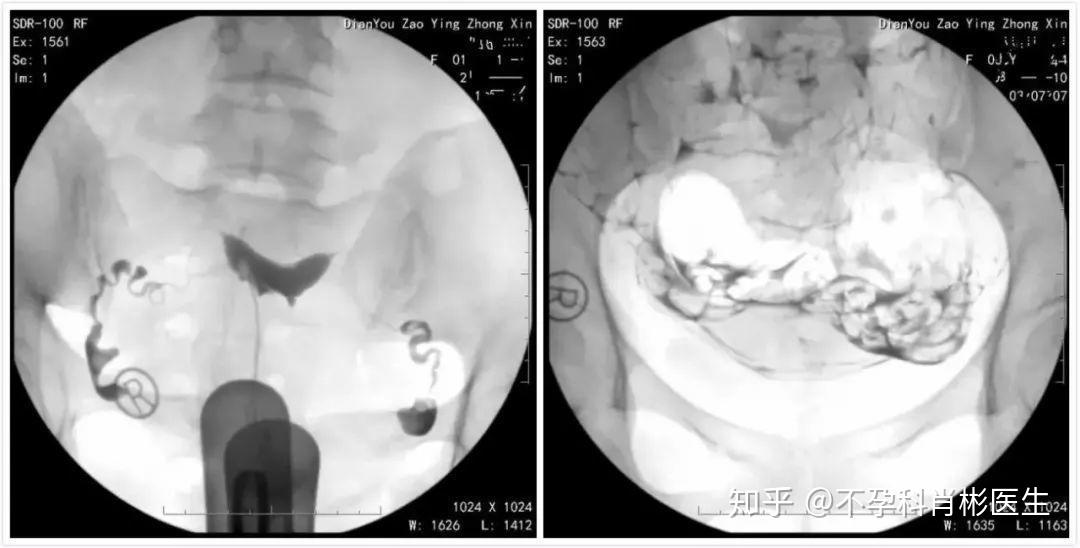

输卵管堵塞咋治?造影后多久能怀孕?手术后需要一段时间的抗结核药物治疗,但这种发生的可能性比较小。 所以有过人流手术史、阑尾炎史、盆腔炎性疾病、盆腔内手术史等的女性备孕超过一年以上未孕者,最好去医院做造影查查输卵管。 输卵管堵塞怎么治疗? 输卵管梗阻、粘连在治疗前需要通过造影检查,粘连的部位,程...